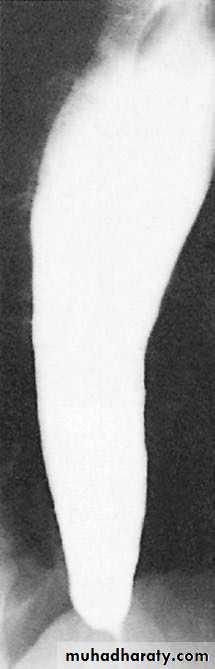

Figure1 : large filling defect by GIST.